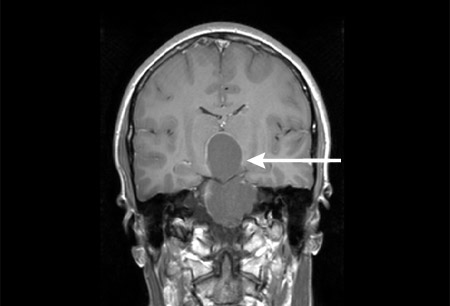

颅咽管瘤是恶性肿瘤吗?一般来说,颅咽管瘤占颅内肿瘤的 6% ~9%,占儿童鞍区肿瘤的54%。 颅咽管瘤不但不是少见疾病,而且是一种儿童较为常见的颅内肿瘤。

颅咽管瘤是恶性肿瘤吗?组织学上颅咽管瘤一般呈良性表现,但即使这样,颅咽管瘤的高复发率、生存质量的低下及无瘤长期生存率低,使颅咽管瘤成为少有的被冠以恶性结果的良性肿瘤。

颅咽管瘤一般多发于儿童期,成年人少见。大多数颅咽管瘤呈间歇性生长,故总体上看肿瘤生长较慢,其症状发展也慢;少数颅咽管瘤生长快速,其病情进展亦较快。颅咽管瘤的治疗一般为手术治疗,但由于肿瘤位置深在,手术治疗具挑战性,而且对于孩子来说,这更是一场高难度的考验。这里就家长们关于颅咽管瘤常见的手术问题,为大家答疑解惑。

颅咽管瘤是恶性肿瘤吗?由于颅咽管瘤为良性肿瘤,除部分与视交叉、灰结节、垂体柄、下丘脑、三脑室底等某处粘连外,大多数与周围组织结构有胶质反应边界或蛛网膜分界,因此原则上应力争做到肿瘤全切除,对儿童患者,以防止复发。一般来说,成功的手术可合适缓解视交叉受压引起的视力、视野改变以及高颅压引起的头痛等症状,还能使腺垂体功能得到恢复。